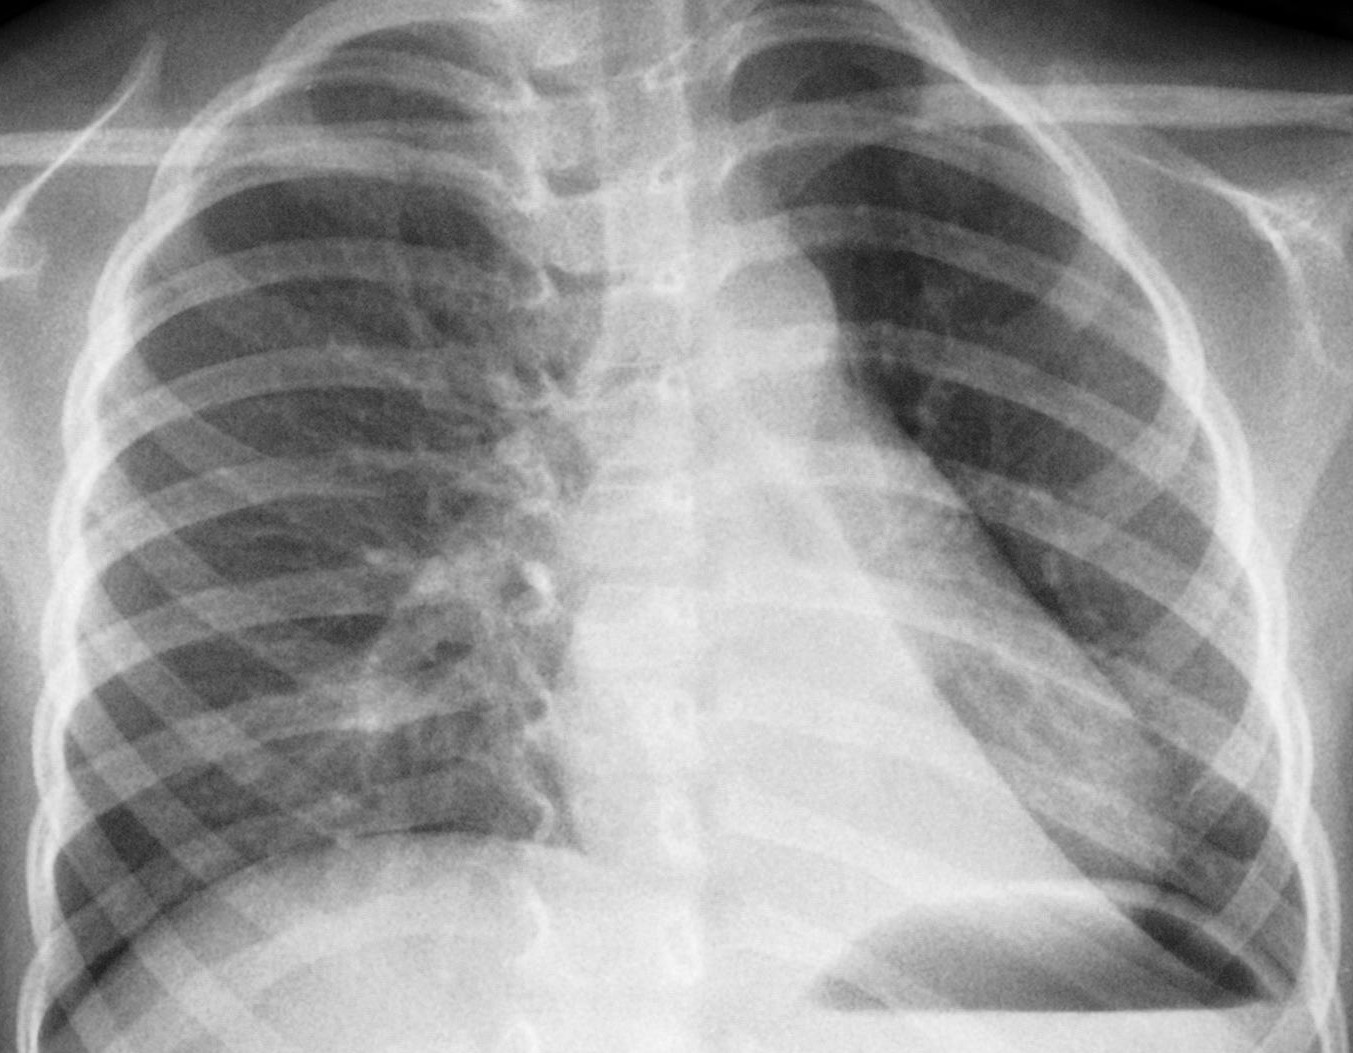

S. � un bambino di 4 anni in cui era stata fatta diagnosi prenatale di malformazione basale sinistra alla 23� settimana di gestazione. A fine gravidanza la lesione non era pi� visibile per cui, dopo la nascita non era pi� stata ricercata. Dall�et� di 2 anni, tuttavia erano comparsi episodi polmonari infettivi recidivanti sempre alla base inferiore di sinistra.

L�Rx torace eseguito in corso di uno di questi episodi aveva evidenziato la presenza di polmonite basale sinistra (Figura 1).

In Figura 3 l�immagine del controllo a un anno dall�intervento.

Figura 3 |